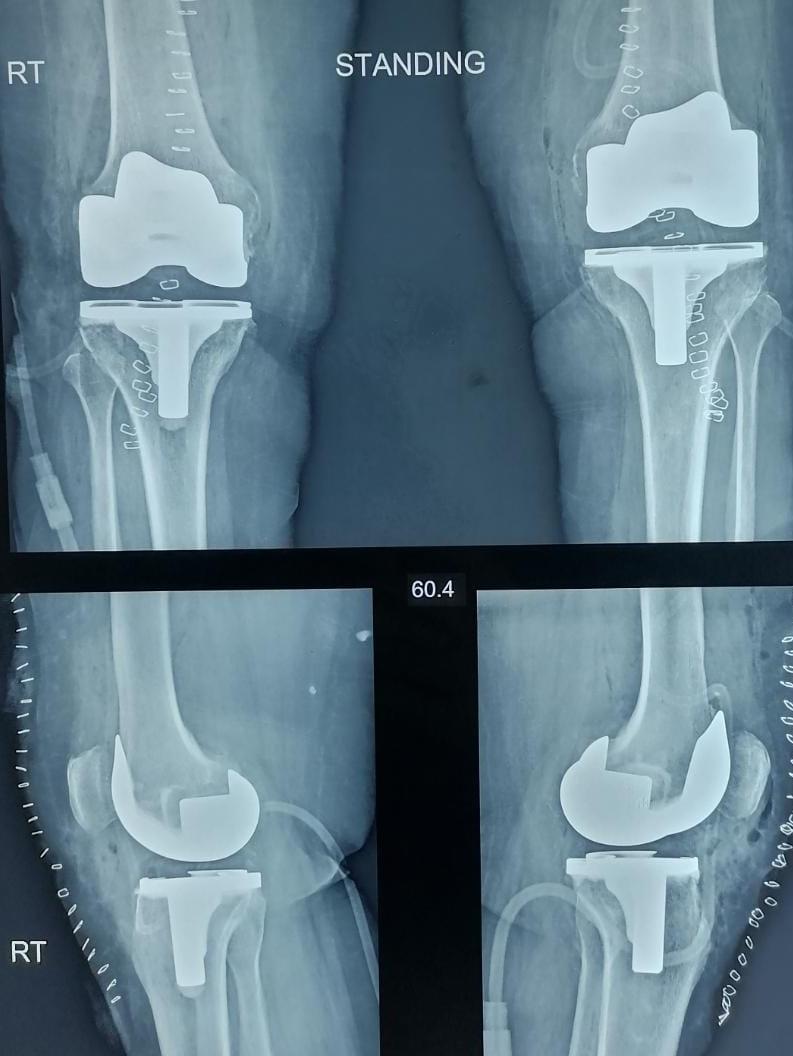

X-ray

Surgeries